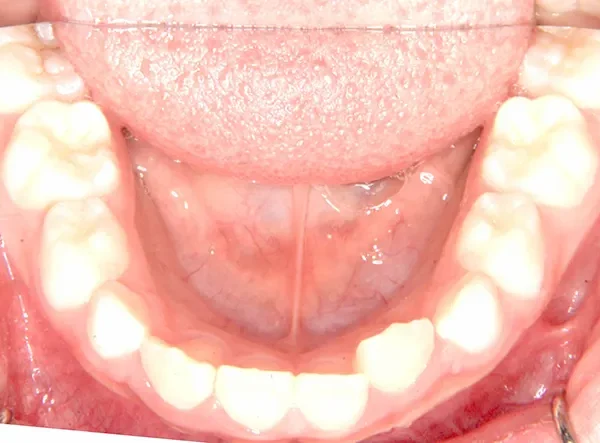

【子供の矯正(一期)】叢生・反対咬合・受け口・非抜歯症例・7歳女児【M.H様】

初診時年齢 小学校1年生 (女性) 主訴 受け口

診断名 叢生・反対咬合 装置名

状態 永久歯が生える隙間がない(叢生)

受け口(下顎前突/反対咬合)

下顎が大きい傾向があります。

上下の真ん中にズレがあるのと、上下とも永久歯の生えるスペースがせまいため、オリジナル矯正装置でスペースを作り、受け口も改善していきます。

治療回数21回、2年7ヶ月の治療期間で矯正治療を終了しました。

主訴が改善され、ご満足頂きました。

初診

治療終了後